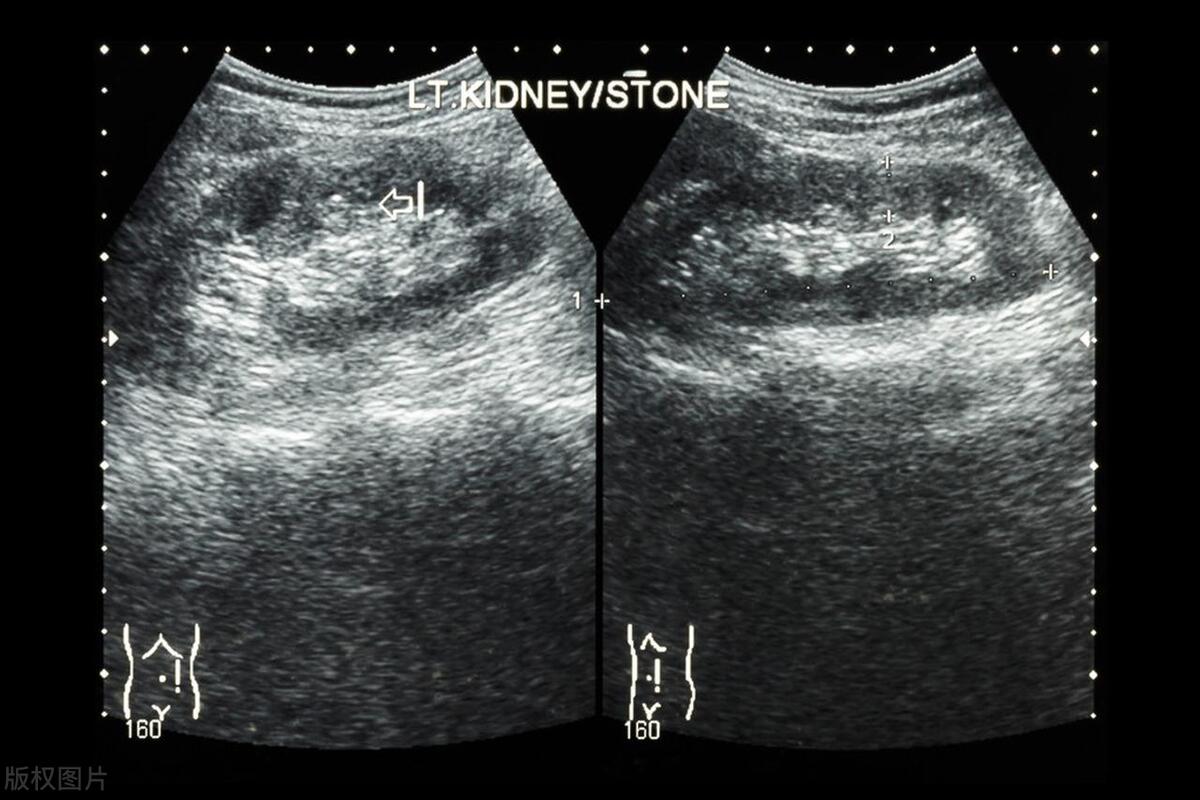

肾结石的早期症状可能并不明显,很多人都是在体检中“意外发现”。因此,定期进行肾脏影像学检查(如B超)非常重要。